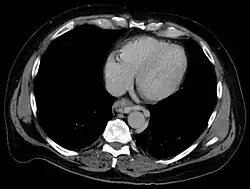

| Diagnostic method | Endoscopy |

Esophageal varices are extremely dilated sub-mucosal veins in the lower third of the esophagus.[1] They are most often a consequence of portal hypertension,[2] commonly due to cirrhosis.[3] People with esophageal varices have a strong tendency to develop severe bleeding which left untreated can be fatal. Esophageal varices are typically diagnosed through an esophagogastroduodenoscopy.[4]

Dilated submucosal veins are the most prominent histologic feature of esophageal varices. The expansion of the submucosa leads to elevation of the mucosa above the surrounding tissue, which is apparent during endoscopy and is a key diagnostic feature. Evidence of recent variceal hemorrhage includes necrosis and ulceration of the mucosa. Evidence of past variceal hemorrhage includes inflammation and venous thrombosis.